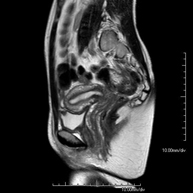

Prueba diagnóstica no invasiva que consiste en la obtención de imágenes de alta definición anatómica de la pelvis mediante el empleo de un campo electromagnético y ondas de radio (con un emisor y un receptor). No utiliza radiación ionizante. Se realiza para estudiar patologías del útero, del ovario, de las trompas y la vagina, ya sean de origen tumoral, inflamatorio o vasculares. Además permite valorar les estructuras adyacentes localizadas en la pelvis, identificando sus alteraciones. A veces requiere el uso de contraste intravenoso (Gadolinio) para caracterizar las lesiones. - RM Pelvis masculina